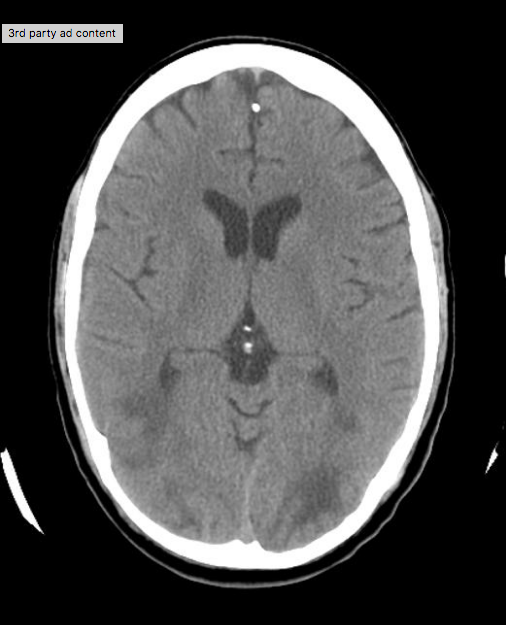

Estudo de imagem para excluir isquemia ou hemorragias

- pode haver atrofia cerebral ou (especialmente em DM) aumento do sinal nas regiões corticais e subcorticais em regiões frontal, parietal e occipital ==> edema localizado

- PRES ou hipersinal bilateral em T2/FLAIR em gânglios da base

Achados

PRES

Referência : https://radiopaedia.org/cases/posterior-reversible-encephalopathy-syndrome-pres?lang=us